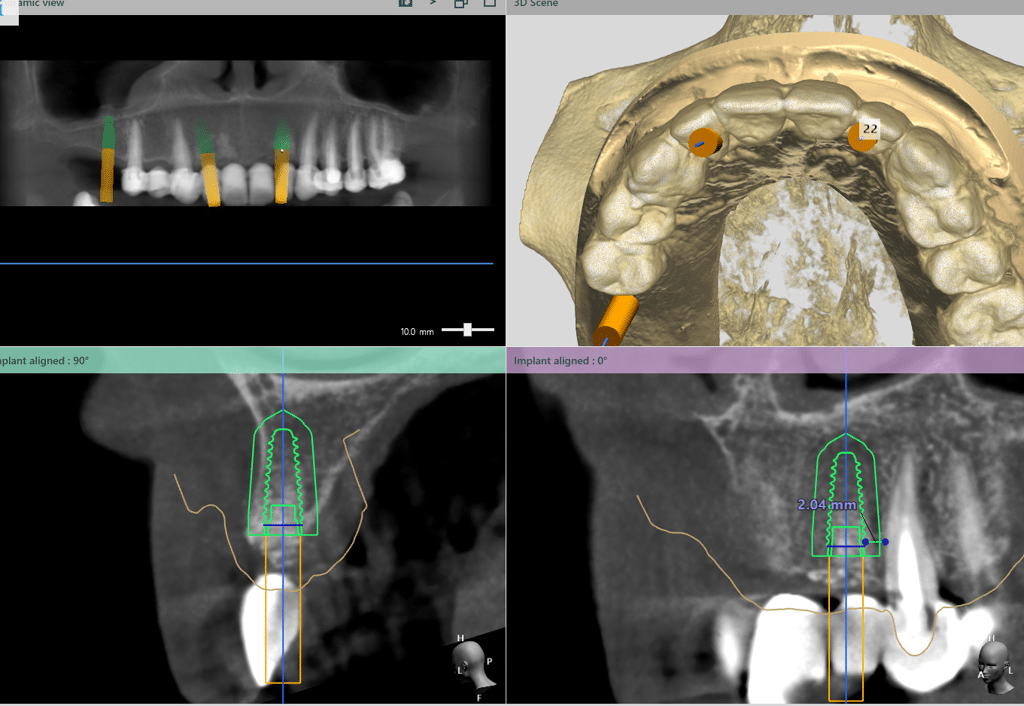

Implanturile vor fi inserate cu ghid chirurgical după 6 luni. Se vor insera implanturi în pozițiile 12, 22, 16, 36, 46.

S-a realizat scanarea digitală a arcadelor și ocluzia pacientului, iar împreună cu tehnicianul radiolog de la DigiRay, Dr. Eliza Drăgan a efectuat în software-ul 3Shape suprapunerea fișierului .stl al amprentei digitale peste fișierul .dcm de la CBCT. Medicul a planificat individual poziția și axul de inserție al fiecărui implant.